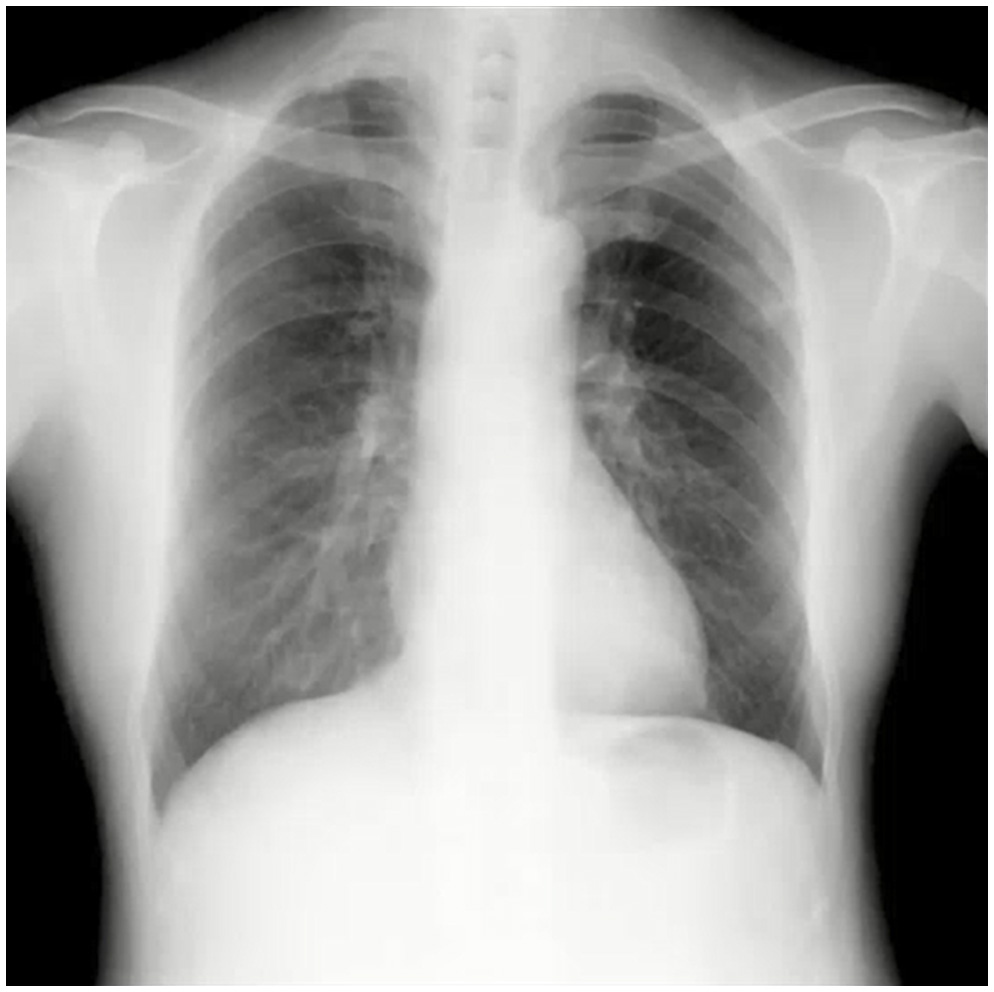

デジタルX線動画撮影システムとは

デジタルX線動画撮影システム(Dynamic Digital Radiography)は従来の単純X線撮影と同様に、一般X線撮影装置を用いて簡便に撮影できる新たな検査法であり、回診用X線撮影装置「AeroDR TX m01」によりベッドサイドでのX線動画撮影が可能となり、更なる広がりを見せています。

| タイトル | DDR臨床セミナー ~胸部単純画像の基本からX線動態画像の臨床での活用まで~ |

本当は教わりたかった!?ポータブル胸部X線写真の読み方 2025 ~動態検査での知見も交えて~ 松本 純一先生 聖マリアンナ医科大学 救急医学 講師 |